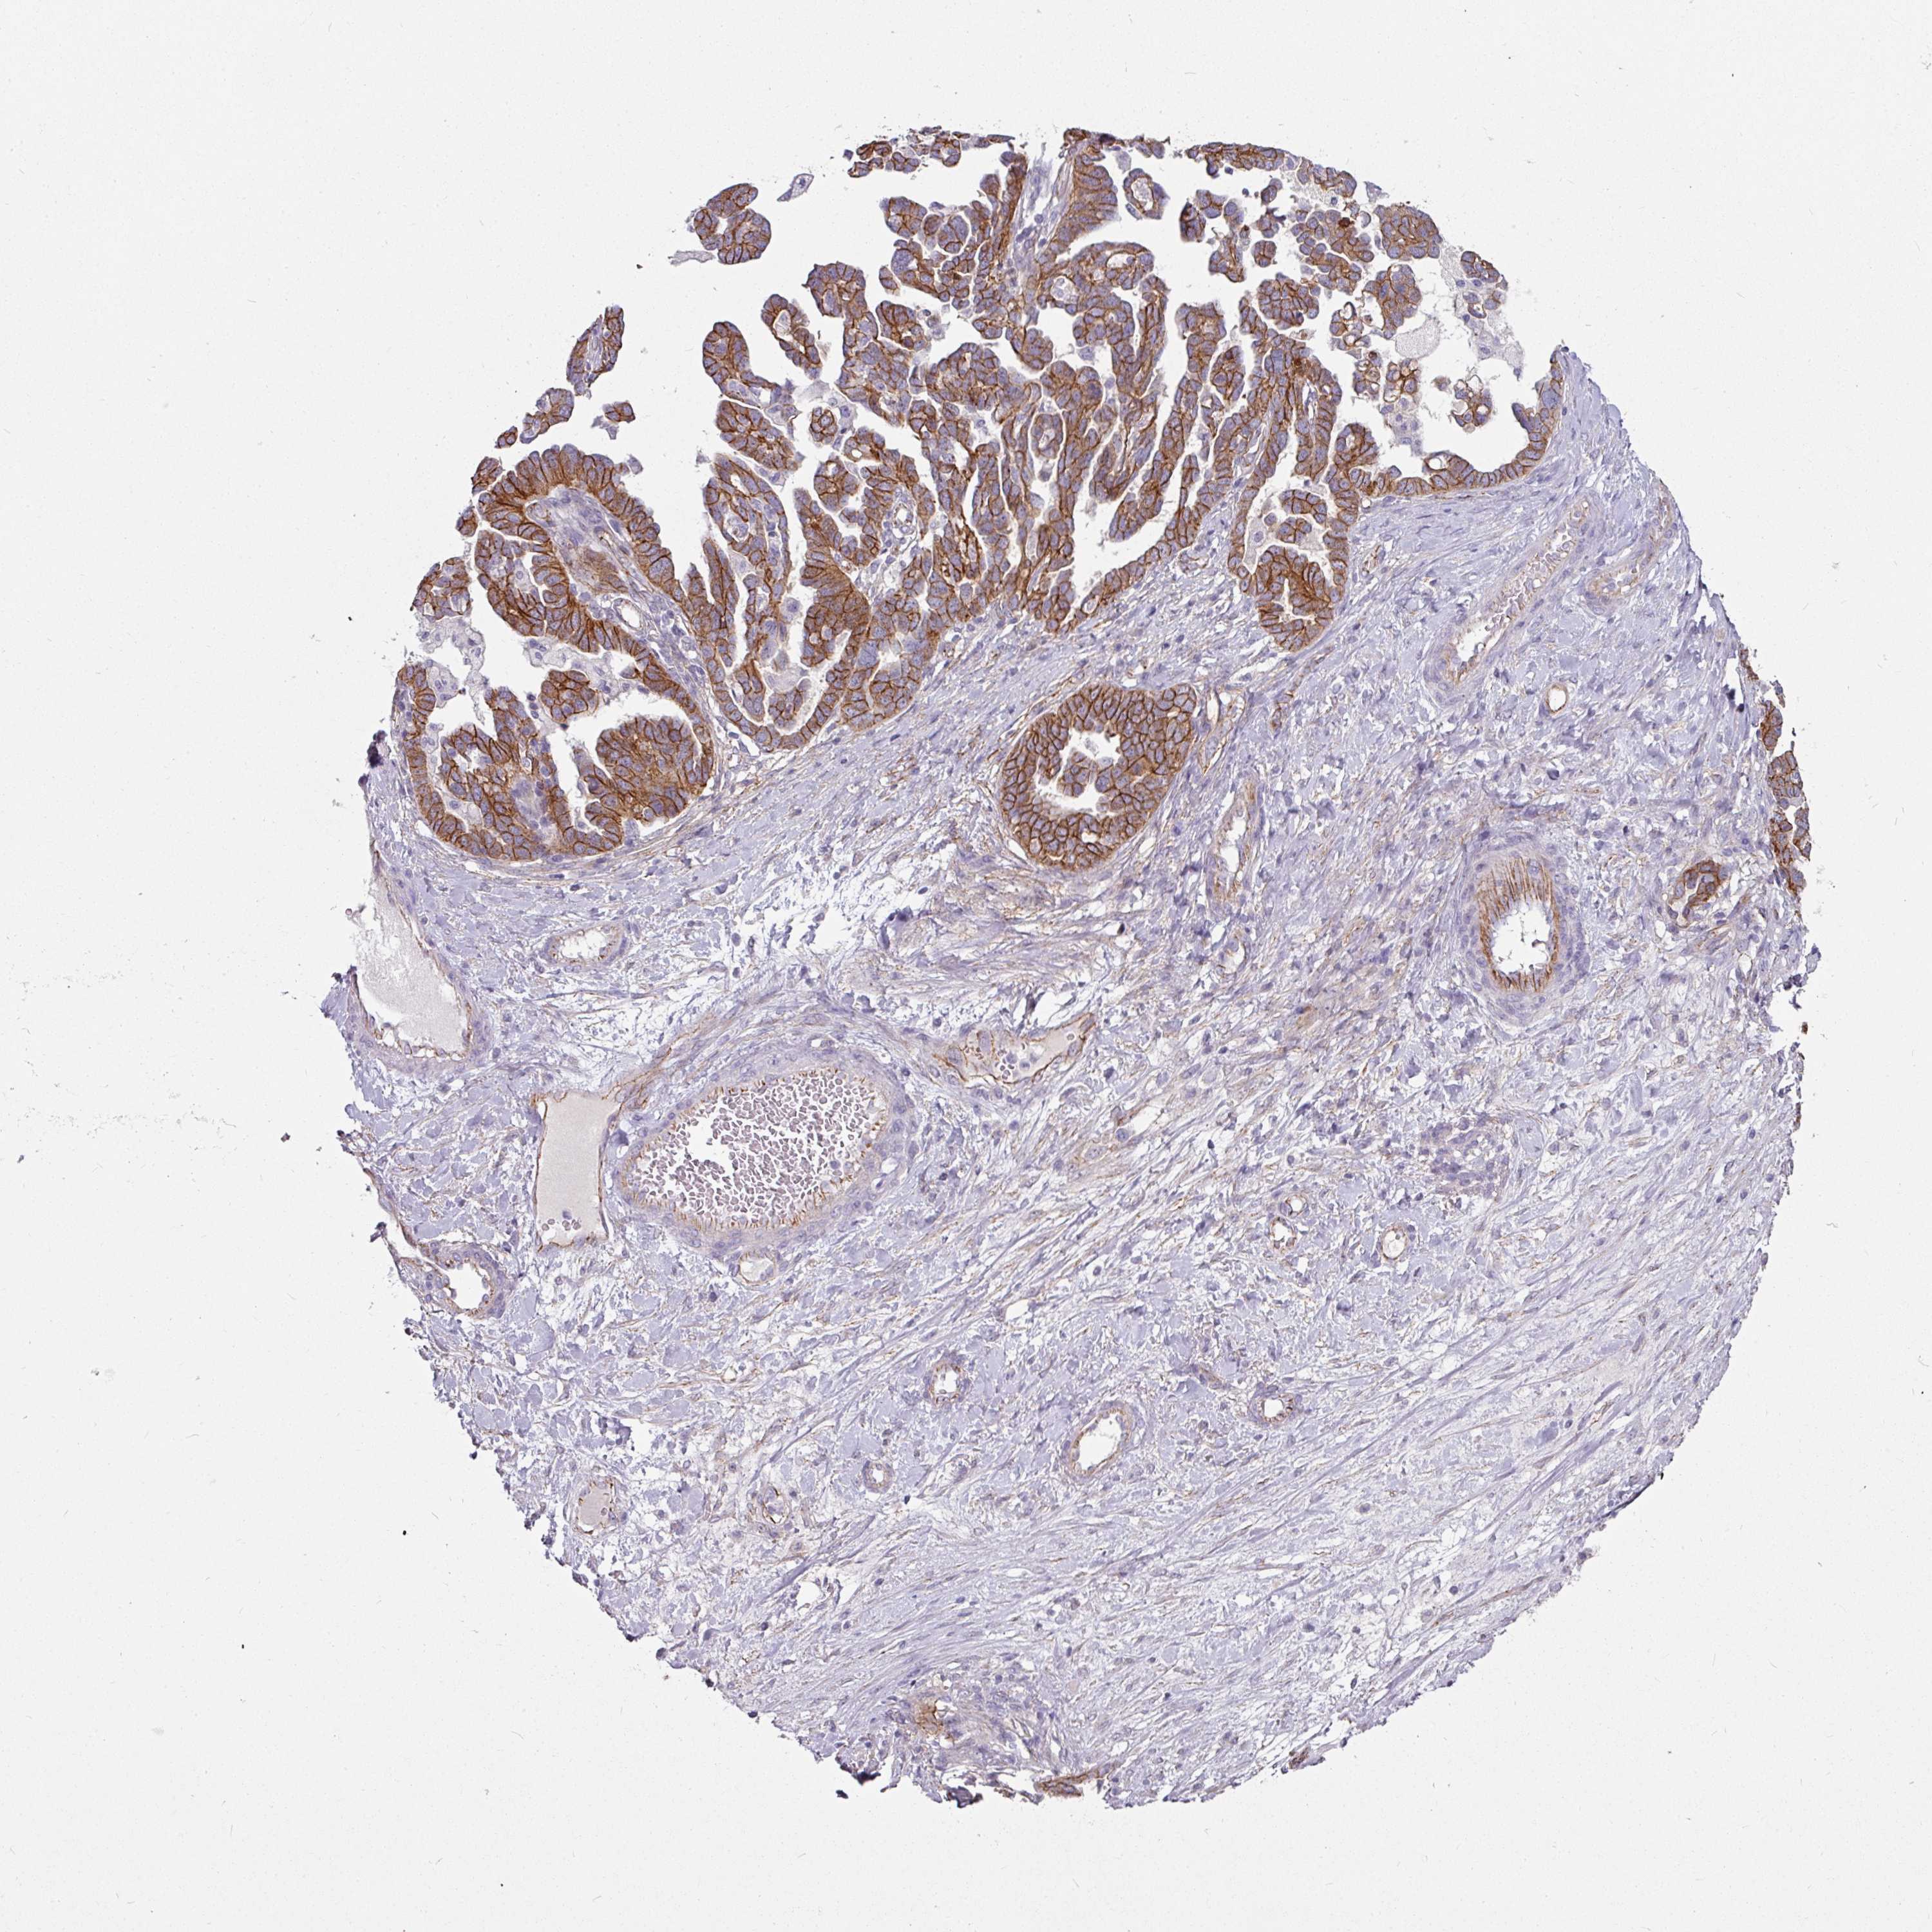

OVARIAN CANCER - Protein expressioni

A mouse-over function shows sample information and annotation data. Click on an image to view it in a full screen mode. Samples can be filtered based on level of antibody staining by selecting one or several of the following categories: high, medium, low and not detected. The assay and annotation is described here.

Note that samples used for immunohistochemistry by the Human Protein Atlas do not correspond to samples in the TCGA dataset.

Antibody stainingi

Antibody staining in the annotated cell types in the current human tissue is reported as not detected, low, medium, or high, based on conventional immunohistochemistry profiling in selected tissues. This score is based on the combination of the staining intensity and fraction of stained cells.

Each image is clickable and will lead to virtual microscopy that enables deeper exploration of all samples and also displays staining intensity scores, fraction scores and subcellular localization as well as patient and tissue information for each sample.

Antibody HPA032047

Antibody CAB002139

Cystadenocarcinoma, serous, NOS

Carcinoma, endometroid